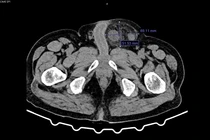

Kết quả chụp X-quang, siêu âm và cắt lớp cho thấy dạ dày chứa nhiều chất đặc quánh, hình ảnh bã thức ăn gây tắc ruột. Người bệnh được chẩn đoán tắc ruột do bã thức ăn, chỉ định phẫu thuật mở dạ dày lấy khối bã. Sau mổ, bác sĩ ghi nhận khối bã lớn, cứng, màu nâu đen, nguyên nhân gây tắc nghẽn kéo dài dẫn đến nhiễm trùng, suy thận cấp và suy đa tạng.